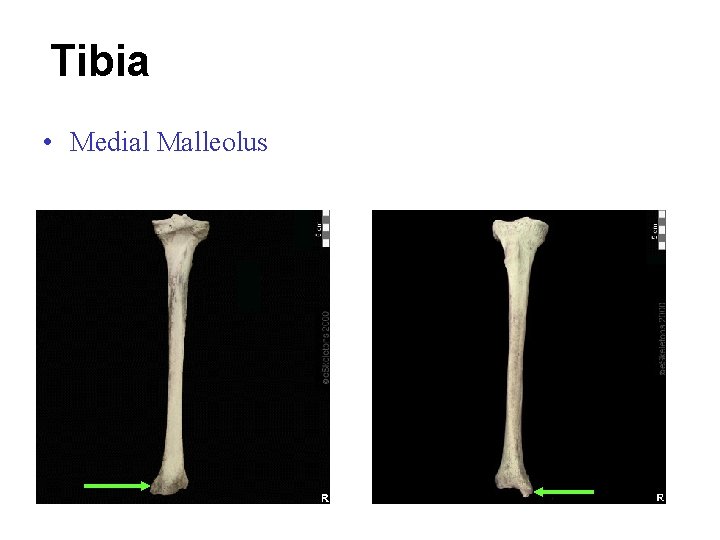

Tibia • Medial Malleolus

Tibia